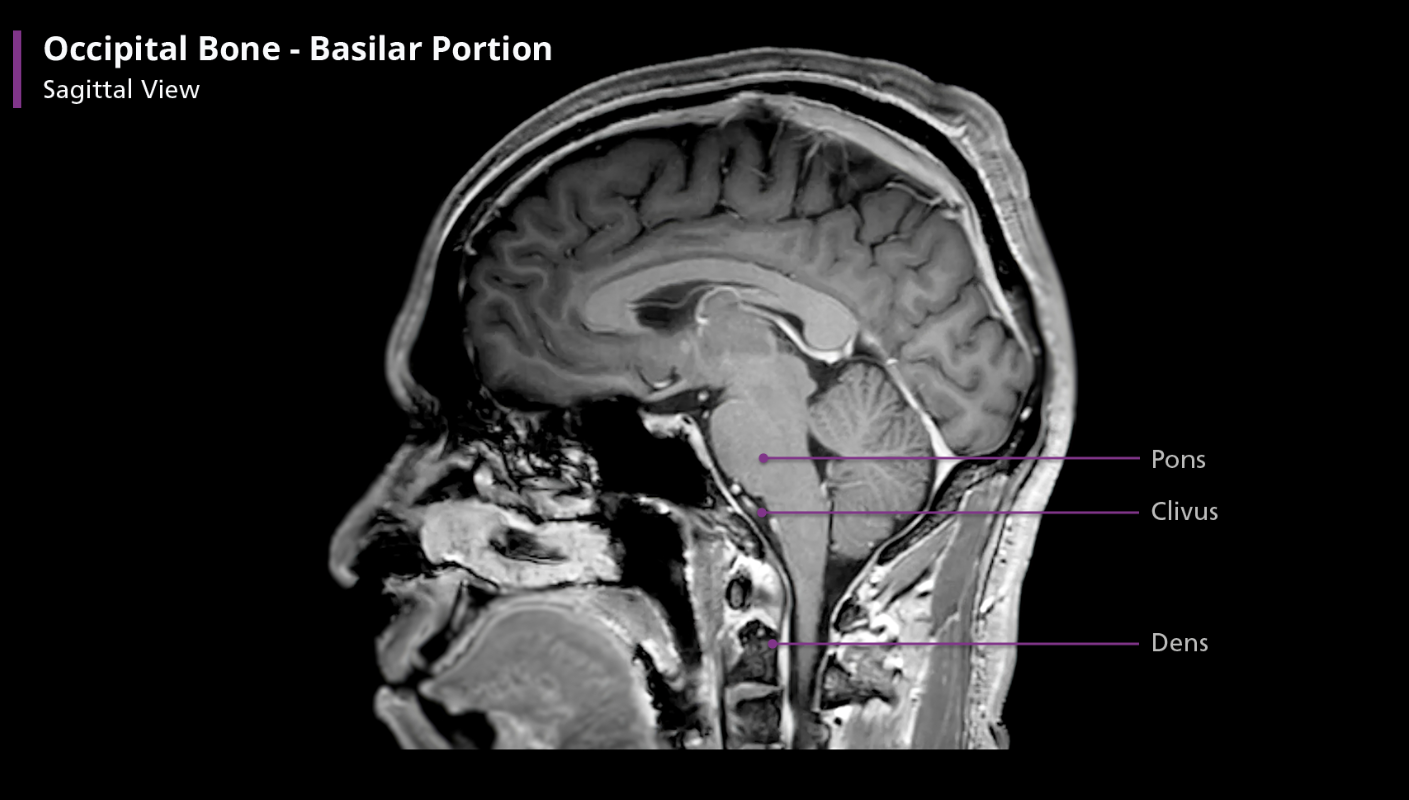

Occipital bone - basilar portion

Anterior to the foramen magnum, the basilar portion articulates with the sphenoid bone by means of a thin plate of cartilage, which becomes ossified by approx. age 25. The very most anterior part of the basilar portion contains a shallow depression and slopes anterosuperiorly before connecting to the sphenoid bone. This part f the bone is called the clivus, which is latin for “slope”

The clivus is important because it supports the pons. If you draw a line from the clivus posteriorly on a sagittal view, it should transect, or at least be tangential to, the dens. If not, there is an atlanto-occipital dislocation, which is often a fatal injury. Incidentally, the clivus contains more fat than other bones, giving it a unique appearance on T1-weighted MR imaging.